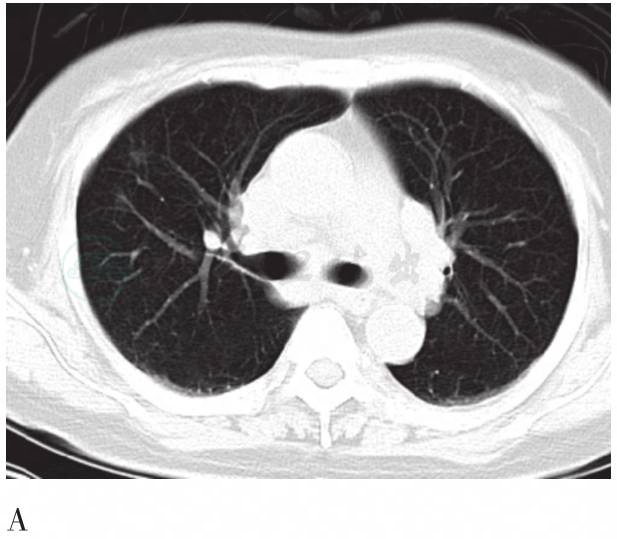

图4 胸部CT横轴位图

A. 激素治疗前肺内多发小斑片影;B. 激素治疗后复查消失;C. 激素治疗后纵隔及肺门淋巴结明显缩小